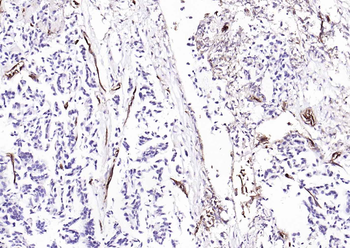

Immunohistochemical staining of paraffin embedded mouse skin tissue using anti-CD31 (primary antibody at 1:200)

Immunohistochemical staining of paraffin embedded mouse skin tissue using CD31 antibody (primary antibody at 1:200)